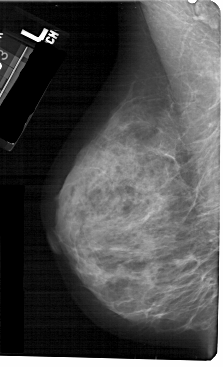

A_1367_1.LEFT_CC

LEFT_CC LINES 5191 PIXELS_PER_LINE 3106 BITS_PER_PIXEL 12 RESOLUTION 43.5 NON_OVERLAY